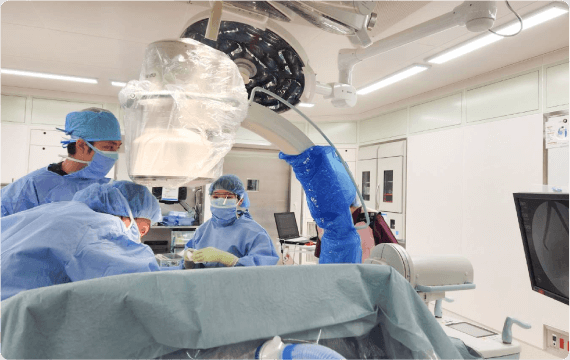

手術・麻酔

シムラ病院では増え続ける手術件数に対応できるよう、手術室を3部屋に増設しました。整形外科領域においては、広島大学四肢外傷講座と連携し、一般外傷から難易度の高い外傷手術まで幅広い整形外傷手術医療を提供しています。また、低侵襲で最先端の高度診療技術を活用した脊椎手術には自信があり、人工関節・スポーツ外傷に至るまで様々な分野における質の高い手術をお約束いたします。

外科領域においては広島大学病院と連携し、呼吸器外科(肺)手術、乳腺手術、一般外科手術も行っており、多くの患者さまに喜んでいただいています。

手術に麻酔は不可欠です、麻酔管理は、手術中の患者さまの痛みをなくし適切に眠った状態にするだけでなく、血圧や脈拍、呼吸を調整して、全身状態を良好に維持する医療行為です。また、手術中だけでなく術後も痛みを和らげ、患者さまを肉体的・精神的な負担から守ります。当院では、麻酔科専門医が患者さまの全身状態を術前に評価し、最適な麻酔法を提供しています。また全身麻酔に様々な種類の区域麻酔(超音波装置を用いて神経の走行に沿って局所麻酔薬を注射する方法)を併用して、術中、術後の痛みの緩和を実施しています。術後の痛みが強い手術では、痛み止めが常に流れる装置をつけて、薬剤師や看護師とのチームで管理して早期回復を目指します。

シムラ病院では増え続ける手術件数に対応できるよう、手術室を3部屋に増設しました。整形外科領域においては、広島大学四肢外傷講座と連携し、一般外傷から難易度の高い外傷手術まで幅広い整形外傷手術医療を提供しています。また、低侵襲で最先端の高度診療技術を活用した脊椎手術には自信があり、人工関節・スポーツ外傷に至るまで様々な分野における質の高い手術をお約束いたします。

外科領域においては広島大学病院と連携し、呼吸器外科(肺)手術、乳腺手術、一般外科手術も行っており、多くの患者さまに喜んでいただいています。

手術に麻酔は不可欠です、麻酔管理は、手術中の患者さまの痛みをなくし適切に眠った状態にするだけでなく、血圧や脈拍、呼吸を調整して、全身状態を良好に維持する医療行為です。また、手術中だけでなく術後も痛みを和らげ、患者さまを肉体的・精神的な負担から守ります。当院では、麻酔科専門医が患者さまの全身状態を術前に評価し、最適な麻酔法を提供しています。また全身麻酔に様々な種類の区域麻酔(超音波装置を用いて神経の走行に沿って局所麻酔薬を注射する方法)を併用して、術中、術後の痛みの緩和を実施しています。術後の痛みが強い手術では、痛み止めが常に流れる装置をつけて、薬剤師や看護師とのチームで管理して早期回復を目指します。